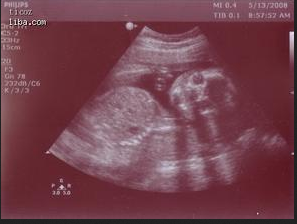

二维彩超图像:

画质:黑白静态成像

优势:静态剖面大致显示腹中胎儿的体表情况

劣势:图像不清晰且需专业人士讲解